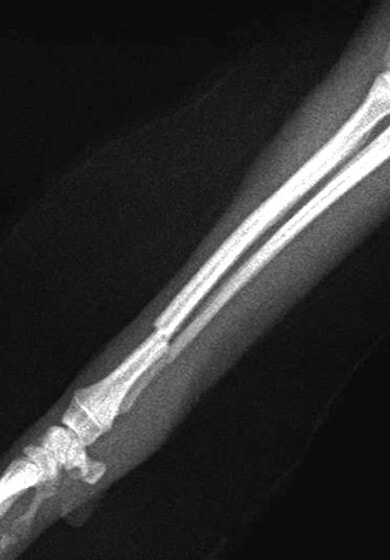

トイプードル 右遠位橈尺骨短斜骨折のALPSによる内固定